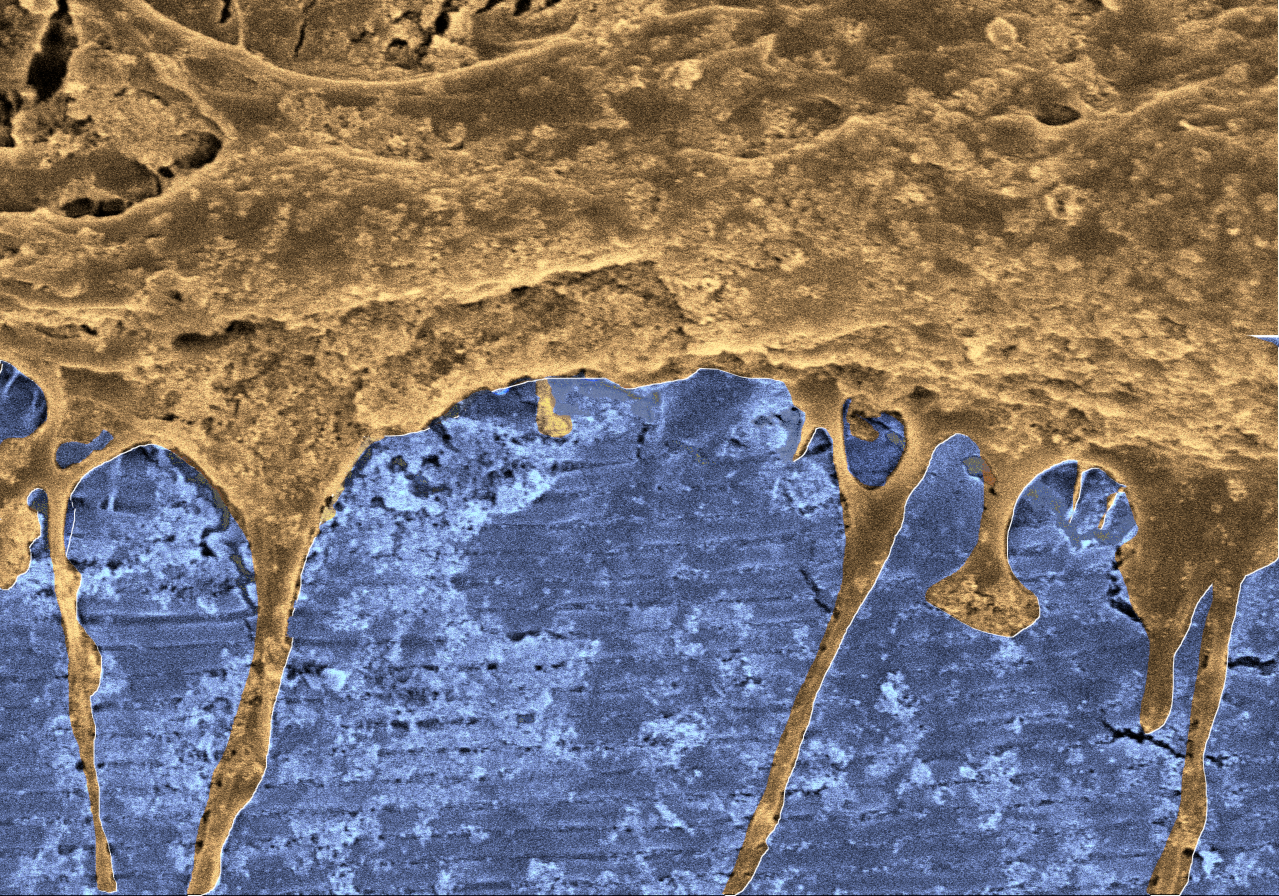

UPV/EHUko Zelulen Biologia eta Histologia Sailaren eta Biomaterial Polimerikoen Zientzia eta Ingeniaritza-ZIBIO Group Taldearen (POLYMAT BERCa) arteko lankidetzari esker, aurrerapen handi bat lortu da terapia zelularrean: “Matrize edo euskarri elastomeriko biobirxurgagarriak ekoitzi ditugu; topografia nanoegituratu ordenatu bat daukate (ildaska-moduko batzuk), eta grafeno-eratorrien bidez euskarriaren gainazala funtzionalizatu dugu”, azaldu du Aitor Larrañaga doktoreak (nanomaterialen diseinu eta karakterizazioan aditua). Euskarri horien bidez, “zelula ama neuralek egituran finkatzea lortu dute, gainazalari atxikitzeko bestelako estaldurarik behar izan gabe. Zelula ama neuralak gai dira, in vitro, euskarri nanoegituratuen gainean diferentziatzeko, eta zelula-taldeek lerrokatuta migratzea lortzen dute, ildo nanoegituratuei jarraiki”, erantsi du José Ramón Pineda doktoreak (zelula amen alorrean aditua).

“Ikerketa honen berritasun nagusia da —azaldu du Larrañaga doktoreak— zelula amen portaera modulatu dezakegula, eta zelulak substratu bati, kasu honetan nanomaterialari, atxikitzea eta norabide jakin batean lerrokatuta haztea lortu dugula. Horrek ateak zabaltzen dizkio halako matrizeak nerbio-ehunaren eskualde kaltetu batean ezarri ahal izateko etorkizuneko aukerari, birsortze eraginkorragoa sustatzeko aukera emango baitu, gaur egungo estrategiekin alderatuta”.

UPV/EHUn lortutako sistema honek aukera ematen du zelula aitzindari neuralen konektagarritasuna berrezartzeko, espazioan zuzen orientatuta; hala, terapia zelularrerako etorkizun handiko tresna bat da, baita nerbio-ehuna birsortzeko ere. “Euskarri nanoegituratu horiek eraginkortasun handia dutela erakutsi dute, baita inkubazio-periodo luzeetarako ere —zeinak bat baitatoz ohiko diferentziazio-protokoloekin—, eta, horrenbestez, tresna optimoa eta ekoizteko erraza dira. Nolanahi ere, esan beharra dago hau hastapenetan dagoela. Zientzia oso mantsoa da; datozen hamarkadetan ikusiko dugunaren oinarriak ezartzen ari gara orain”, adierazi dute, amaitzeko, ikertzaile biek.